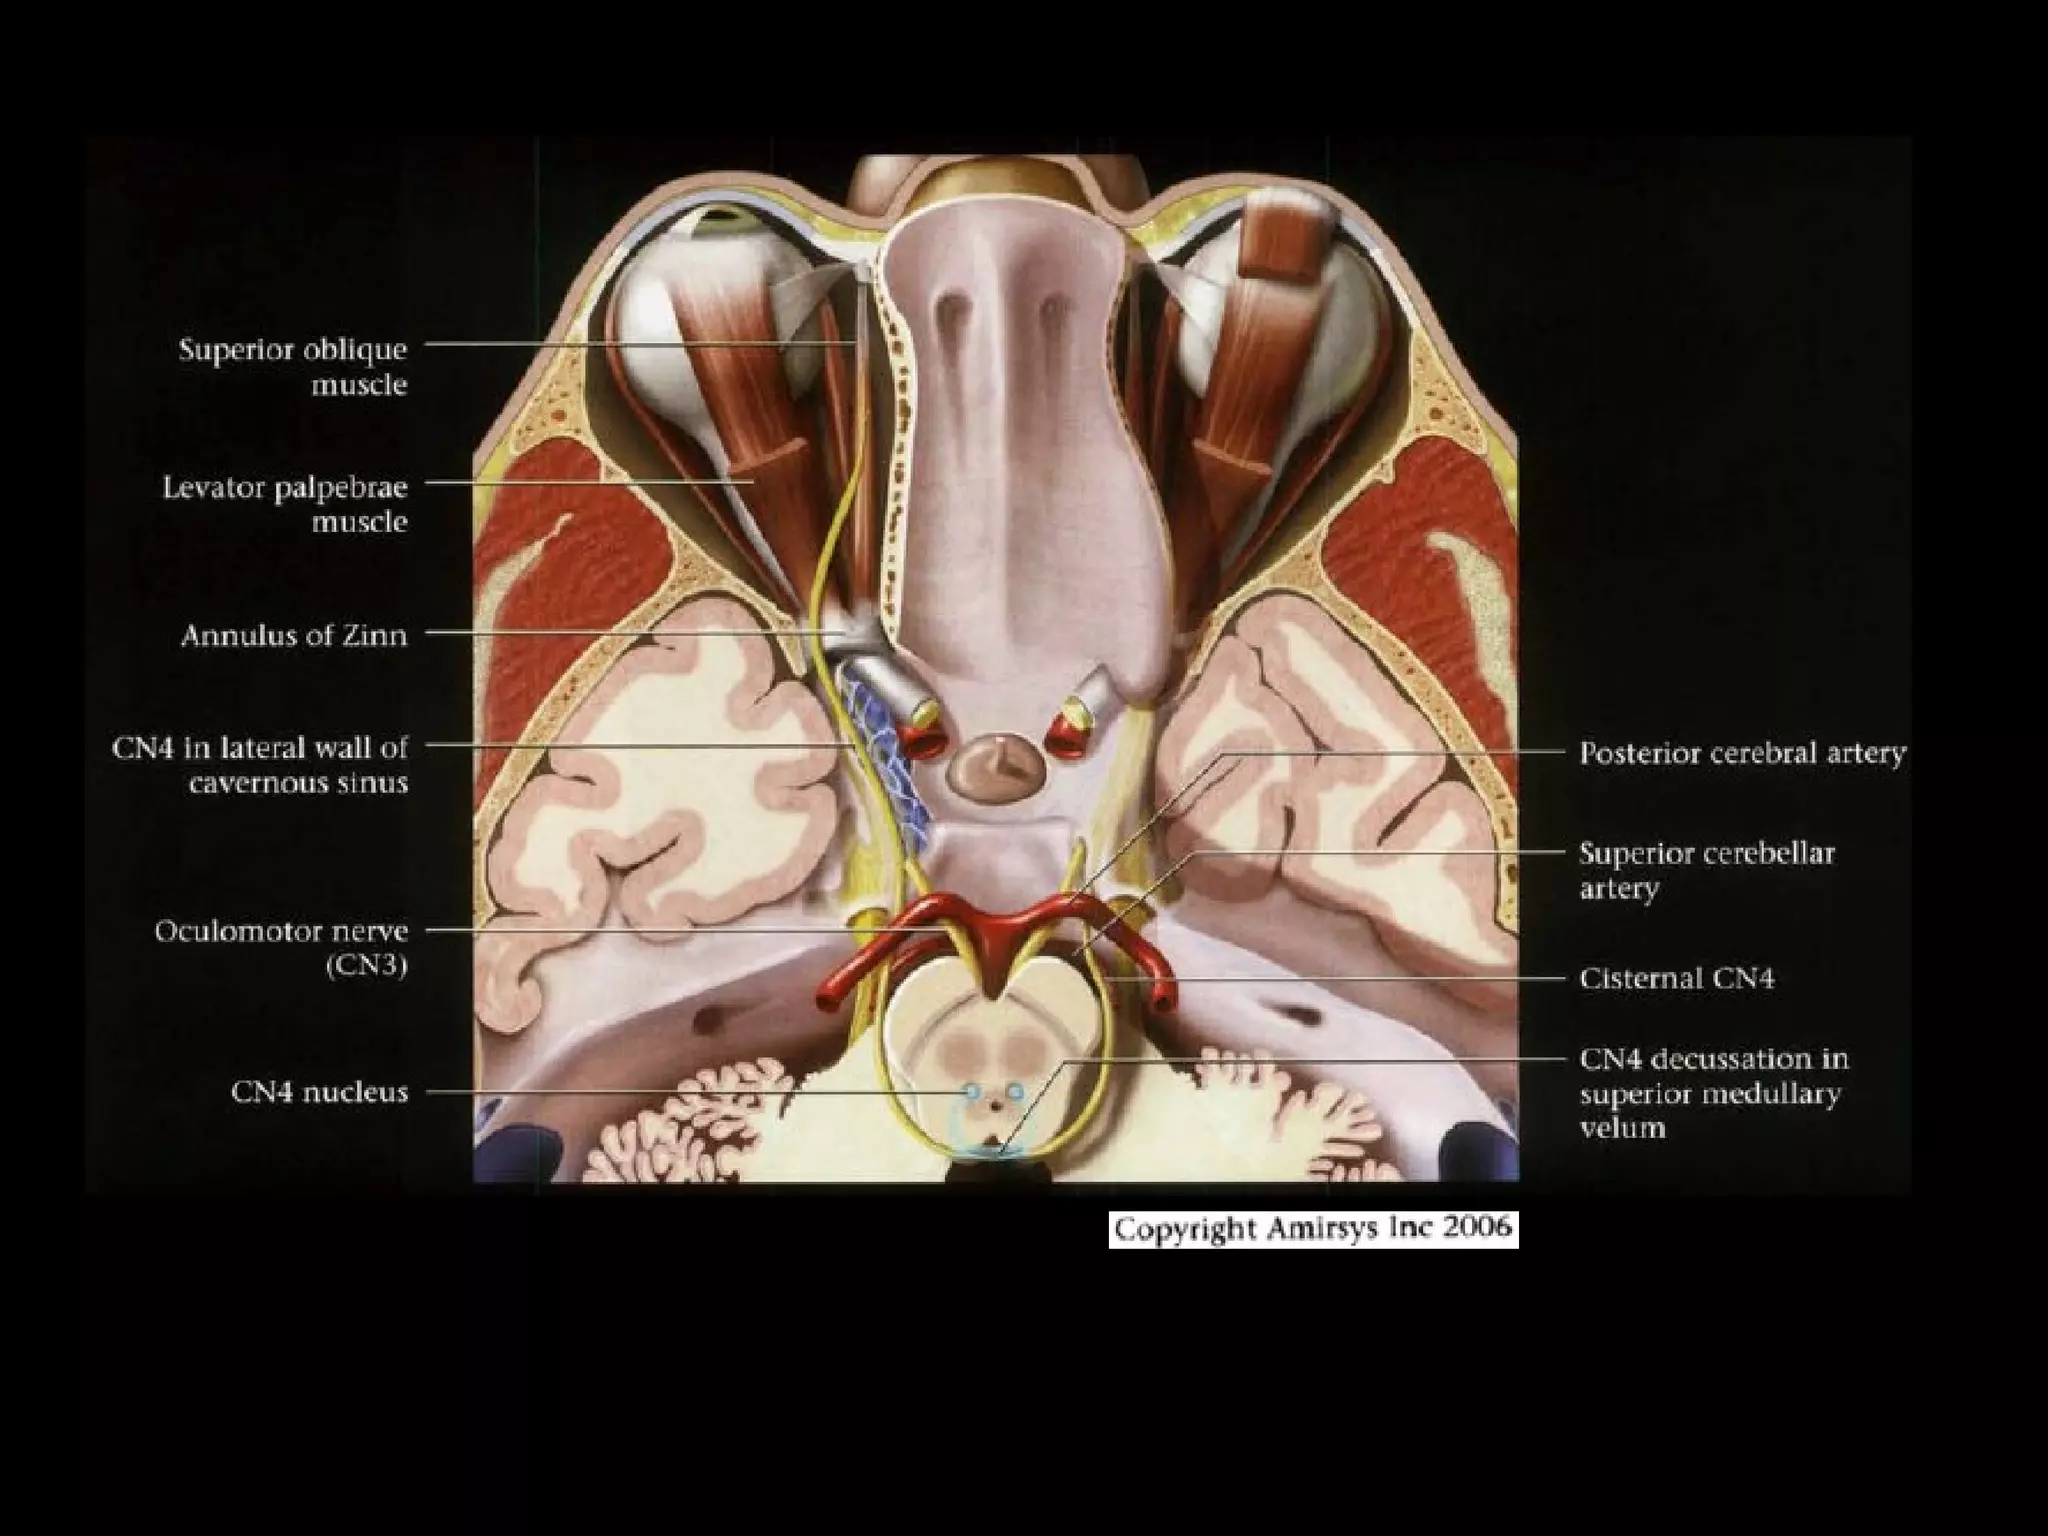

Cranial Nerve III:

The Oculomotor Nerve

• The oculomotor nerve originates from nuclei deep to the

superior colliculus, ventral to the cerebral aqueduct, and

inferior to the pineal gland.

• The nerve then travels across the midbrain from

posterior to anterior.

• The oculomotor nerve root emerges into the

interpeduncular cistern, and this root entry zone in the

cistern is a good way to identify the oculomotor nerve on

axial SSFP MR images.

• In the prepontine cistern, the nerve travels between the

superior cerebellar and posterior cerebral arteries, which

makes it easy to identify on coronal SSFP images.

RadioGraphics 2009; 29:1045–1055

• The cavernous segment of the oculomotor nerve

runs along the lateral wall of the cavernous sinus

and is the most superior of the nerves in this

sinus.

• The oculomotor nerve then enters the orbit

through the superior orbital fissure, before

splitting into superior and inferior divisions lateral

to the optic nerve.

• Knowledge of this anatomy may be helpful for

identifying the precise location of a nerve

abnormality.

Cranial Nerve IV:

The Trochlear Nerve

• The trochlear nerve is the only nerve with a root

entry zone arising from the dorsal (posterior)

brainstem.

• After exiting the pons, the trochlear nerve curves

forward over the superior cerebellar peduncle,

then runs alongside the oculomotor nerve

between the posterior cerebral and superior

cerebellar arteries.

• The trochlear nerve then pierces the dura to

enter the cisterna basalis between the free and

attached borders of the cerebellar tentorium.

• After completing its cisternal course, the

trochlear nerve runs through the lateral

cavernous sinus just below the oculomotor

nerve and enters the orbit through the

superior orbital fissure to innervate the

superior oblique muscle.

• The nerve is named for the trochlea, the

fibrous pulley through which the tendon of

the superior oblique muscle passes.